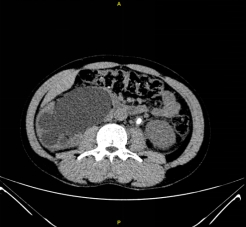

入院后,三维CT发现患者双侧输尿管结石,右肾盂输尿管连接处狭窄,右肾严重积水,左肾也因结石梗阻导致肾盂输尿管积水。肌酐1284.5μmoI/L,已经达到急性肾功能不全(尿毒症期)。王春阳教授立即为患者进行超声引导下右肾穿刺造瘘,改善患者肾功能,并制定拟行机器人辅助腹腔镜下双侧输尿管切开取石术+机器人辅助腹腔镜下右侧肾盂成型肾盂输尿管再吻合术,决定一次手术解决目前导致患者肾脏积水的全部问题。

王春阳教授介绍,仅利用一次手术同时处理患者全部问题,大大增加手术难度,但能减轻患者的痛苦和费用。对于结石大、梗阻明显、结石坎顿的病人,为及时解决梗阻,挽救肾功能,可选择输尿管切开取石。传统的输尿管切开取石手术疗效可靠,但患者手术创伤大,恢复慢,住院时间长。运用机器人辅助腹腔镜下行输尿管切开取石术不切断肌肉,不损伤较大血管神经,手术直视下进行,术野可放大10倍,手术损伤小,出血少,恢复快。同时该病人CT中表现出右侧肾盂输尿管连接部狭窄,切开取石后行右侧肾盂成形术,去除狭窄段,对肾盂输尿管连接部重新塑形,显著解除梗阻。